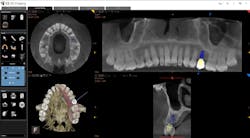

Whether it is an implant consultation for a single implant (figure 4), multiple implants, or full-mouth reconstruction, advanced 3-D software, such as the CS 3D Imaging software, offers you the ability to virtually plan the implant placement in regard to bone height, width, and density with respect to anatomical structures. Once planned, this information is reviewed with the patient in a clear and concise way that is easily understood (figure 5). In my experience, patients often state that they didn’t know that this type of technology was even possible within a dental office. Because of these reasons and more, I have found that case acceptance has gone up exponentially.

Figure 4: Planning an implant in CBCT software